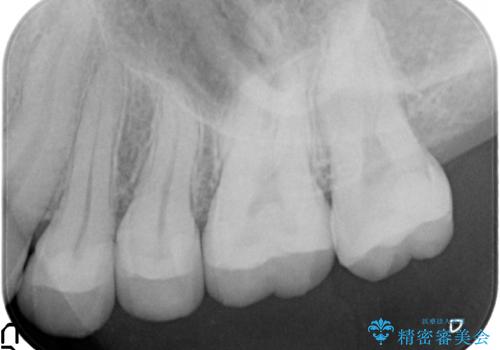

- 他院で治療途中で放置したところを治療したいとご来院されました。

仮づめはフロスもできないため、不潔になりやすく長期的には虫歯になりやすいです。

仮づめの状態でしたが、そこまで中は虫歯になっておらず、神経の治療も不要でした。